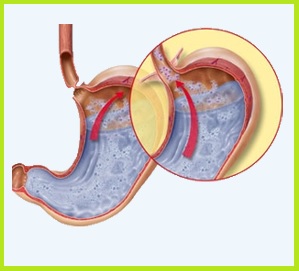

Choroba refluksowa przełyku (ang. gastroesophageal reflux disease, w skrócie GERD) – to schorzenie, które dotyka coraz więcej osób. Męczący problem cofania się treści pokarmu potrafi zaburzyć nam dzień a nawet całą noc.

Refluks potrafi występować nawet w środku nocy. Osoby cierpiące z tytułu refluksu nie powinny leżeć wtedy na płasko. Zaleca się uniesienie torsu pod kątem co najmniej 45º. Wiadomo jednak, że spanie pod takim kątem, nie kojarzy się z czymś przyjemnym, ponieważ każdy z nas chciałby spać tak jak lubi.